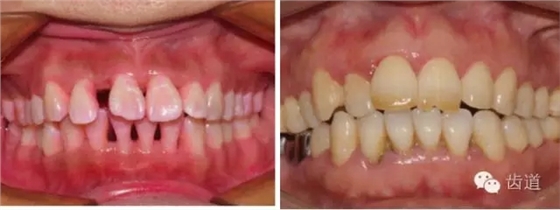

2、牙齦

(顏色、形狀、質(zhì)地、退縮、BOP、PD、附著齦)